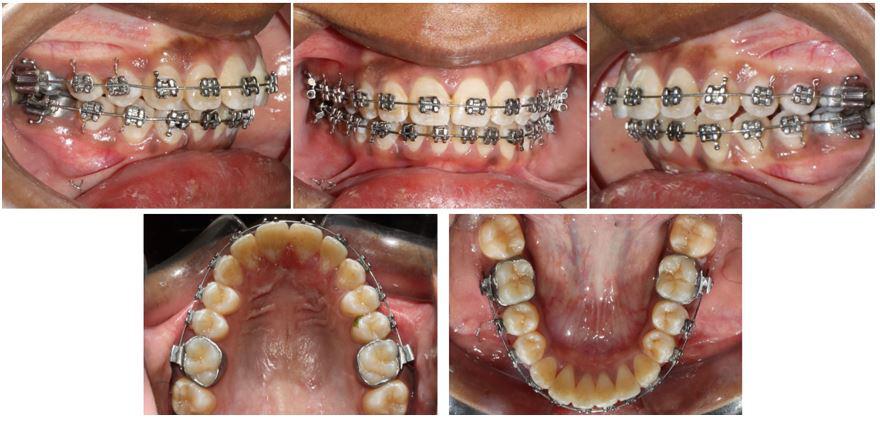

All selfies at T0 and T1 were cropped up to the clavicle of the subject if visible. The backgrounds of the selfies were removed and turned white with the help of Adobe Photoshop CC 2020 version 21.1 software package (Adobe Systems, San Jose, CA). One example of pre-treatment and post-treatment selfies of a subject in skeletal class I is illustrated in Figure 1A and 1B, in skeletal

Figure 1: Skeletal Class I Group (SCI) Male.

A-Pre-treatment (T0) Selfie; B- Post-treatment (T1) Selfie; C. Pretreatment Profile Silhouette (T0). D. Post-treatment Profile Silhouette

Figure 2: Skeletal Class II Group (SCII) Female.

A-Pre-treatment Selfie (T0), B- Post-treatment Selfie (T1). C. Pretreatment Profile Silhouette (T0), D. Post-treatment Profile Silhouette (T1).

Figure 3: Skeletal Class II Group (SCII) Female.

class II is illustrated in Figure 2A and 2B, and in skeletal class III is illustrated in Figures 3A and 3B.

All profile photographs at T0 and T1 were cropped up to the clavicle of the subject. Profile photographs were converted into black silhouettes against a white background using Adobe Photoshop CC 2020 version 21.1 software package (Adobe Systems, San Jose, CA) One example of pre-treatment and posttreatment profile silhouettes of a subject in skeletal class I is illustrated in Figure 1C and 1D, in skeletal class II is illustrated in Figure 2C and 2D, and in skeletal class III is illustrated in Figure 3C and 3D.